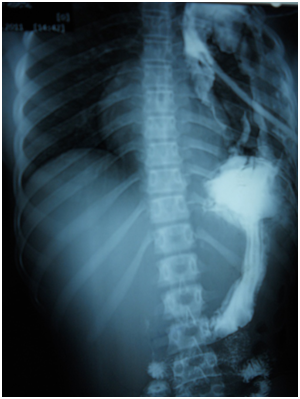

A 17-year-old girl (170cm, 60kg) presented to the emergency department with dyspnea and chest pain after a penetrating stab wound to the chest in the left sixth intercostal space mid-clavicular line, which happened 2hours earlier. Upon physical examination, Pulse was 96 beats per minute and blood pressure was 110/70mmHg, diminished air entry was noticed on the left side of chest. Chest x-ray revealed left hydropneumothorax. Tube thoracostomy was performed left intercostals tube was inserted for drainage. Post-insertion chest x-ray revealed no improvement in the picture of air fluid level (Figure 1) (Figure 2) which was further evaluated by CT that showed fluid collection posteriorly and air anteriorly (Figure 3) (Figure 4). Two days later patient had fever with vomiting and leucocytosis. The nature of the drain from the intercostal tube becomes serosangenous and less hemorrhagic with change in color associated with food. Methylene blue dye (1% concentration) taken orally by the patient was detected in the drain of the intercostal tube two minutes after ingestion (Figure 5). Oral contrast chest x-ray was done, two shots were taken one on swallowing gastrographin, it showed the esophagus outlined without any leakage (Figure 6A). The other shot taken two minutes after oral administration of gastrographin in trendlenberg position, the contrast outlined a track passing from the fundus of the stomach to the left pleural cavity and to the intercostals tube (Figures 6B) (Figure 6C). Laparotomy was performed via midline incision and findings were confirmed. It showed a 3cm orifice of the left copula of the diaphragm with a tear in the gastric fundus which was closed in two layers and the diaphragmatic tear was closed directly with continuous sutures. Two weeks later patient complicated by left empyema with thickened pleura. Thoracotomy was done for complete evacuation of pus and decortication. The patient fully recovered and was discharged 8days after thoracotomy.

Figure 1 Post intercostals tube insertion chest X-ray.

Figure 2 Second day post intercostals tube insertion chest X-ray.